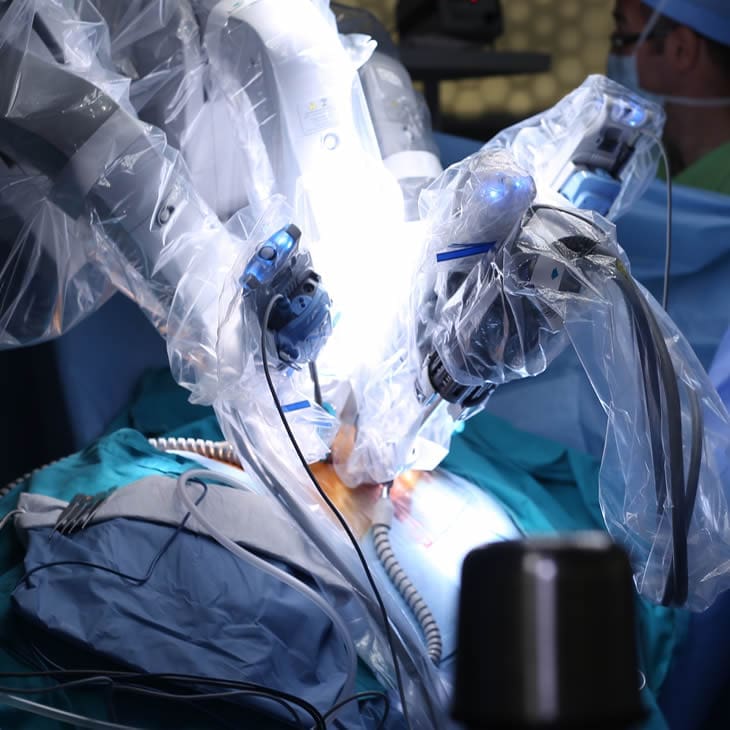

Robot-Assisted Laparoscopic Radical Prostatectomy

The surgical removal of the entire prostate gland and seminal vesicles is a treatment option for men with intermediate or high-risk cancer that has not spread beyond the prostate. Unlike open radical prostatectomy that requires a large incision in the abdomen, Urology Partners surgeons use the da Vinci Surgical® System to perform a robot-assisted laparoscopic radical prostatectomy.

The procedure requires only small abdominal incisions to accommodate a slim robotic arm controlled by the surgeon. A high-definition camera provides a clear, magnified view of the patient’s anatomy, and precision tools give the surgeon the delicate control needed to remove cancerous tissue without damaging surrounding nerves.

In experienced hands, patients who undergo a robot-assisted prostatectomy lose less blood, heal more quickly, have a shorter hospital stay and return to normal activities more quickly.

Today, survivor rates 15 years post-prostatectomy are as high as 93 percent. Urology Partners has some of the most experienced robotic surgeons in the United States—skilled surgeons who have been performing robotic surgery since its early inception in 2002.